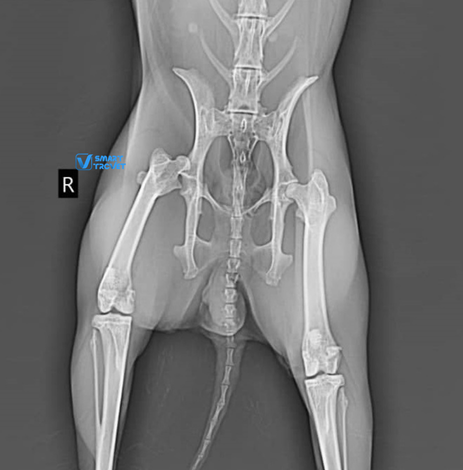

Lili, a two-year-old female rabbit, fell from her owner’s arms, resulting in lameness of the right leg. Radiographs of the pelvis and right hindlimb (excluding the area from mid-tibia to foot) were prepared and found to be of good quality. The radiographs revealed a complete luxation of the right coxofemoral joint, with a dorso-cranial displacement. Both acetabula and the left hip appeared normal. Hip dysplasia was not present. All other bones and joints of the hind limbs were normal, with no additional radiographic abnormalities identified. The final diagnosis, based on the radiographic findings, was traumatic dorso-cranial luxation of the right hip joint.